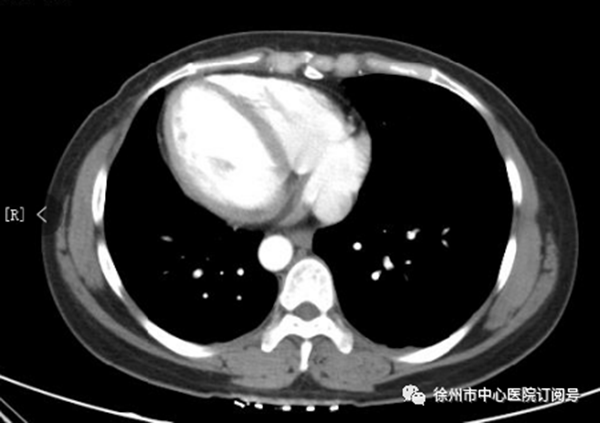

患者的心臟位置右側(cè)